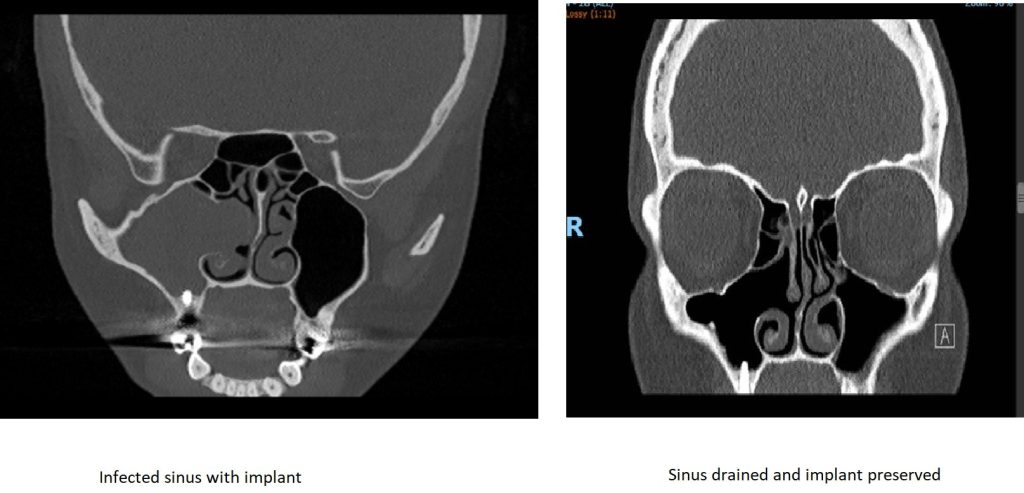

In Figure 2 the maxillary sinus is opaque (infected) due to chronic sinusitis before surgery. This resulted in infection of the zygoma implant and the patient presented with pus discharging through the skin over the zygoma area. The zygoma implant is described as running between the sinus bone and its mucosa, however when this area is infected, a drainage route is created when the bone is perforated and the sinus mucosa is infected and fragile. In this case the infection was drained by FESS and once sinus ventilation was re-established, the infection settled and we managed to preserve the zygoma implant.

Figure 3 is a good example of implant preservation. This patient presented with psudomonas infection of the right maxillary sinus endangering the viability of the dental implant. The infection was drained by FESS and a few months later the patient had a repeat scan which showed complete resolution of the infection, ventilation of the maxillary sinus and the implant intact and secure.